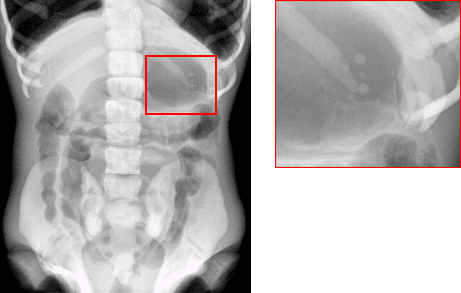

| 진단 분야 | 진단 유형 |

|---|---|

| 폐 | 폐렴, 결핵, 악성 종양 |

| 근골격계 | 뼈 골절, 침식, 골형성 골종, 악성 종양 |

| GIT | 위장관, 신장 병리, 비뇨기계의 GIT 대조 검사 |

| 이비인후과 | 부비강 병리 |